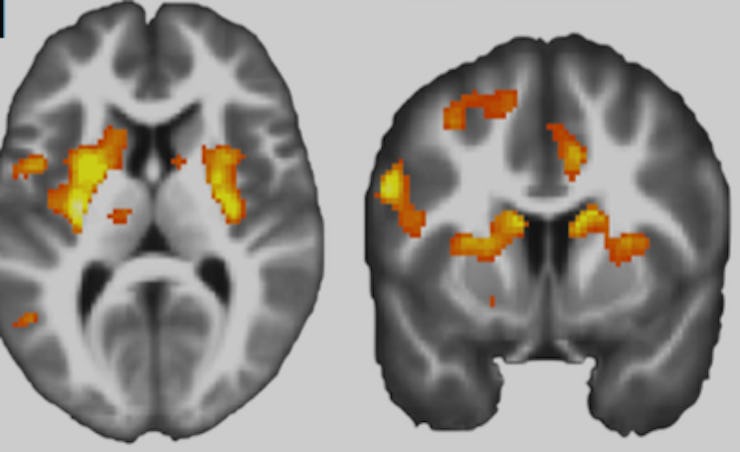

Turns out that people don’t feel too great about paying to hurt others and that this can be seen in the brain. “Most participants displayed moral preferences, placing a higher cost on harming others than themselves,” the researchers write. They found that in the subjects who did decide to shock a stranger in order to earn money, the area of the brain associated with reward and decision-making, the dorsal striatum, was less active than it was when the subjects shocked themselves instead. This regulation seemed to be modulated by the lateral prefrontal cortex, the area of the brain associated with thoughtful action.

In test subjects with stronger moral preferences, the dorsal striatum was less responsive to profit gained from harming others.than profit gained from harming oneself.

Moral systems universally prohibit harming others for personal gain. However, we know little about how such principles guide moral behavior. Using a task that assesses the financial cost participants ascribe to harming others versus themselves, we probed the relationship between moral behavior and neural representations of profit and pain. Most participants displayed moral preferences, placing a higher cost on harming others than themselves. Moral preferences correlated with neural responses to profit, where participants with stronger moral preferences had lower dorsal striatal responses to profit gained from harming others. Lateral prefrontal cortex encoded profit gained from harming others, but not self, and tracked the blameworthiness of harmful choices. Moral decisions also modulated functional connectivity between lateral prefrontal cortex and the profit-sensitive region of dorsal striatum. The findings suggest moral behavior in our task is linked to a neural devaluation of reward realized by a prefrontal modulation of striatal value representations.